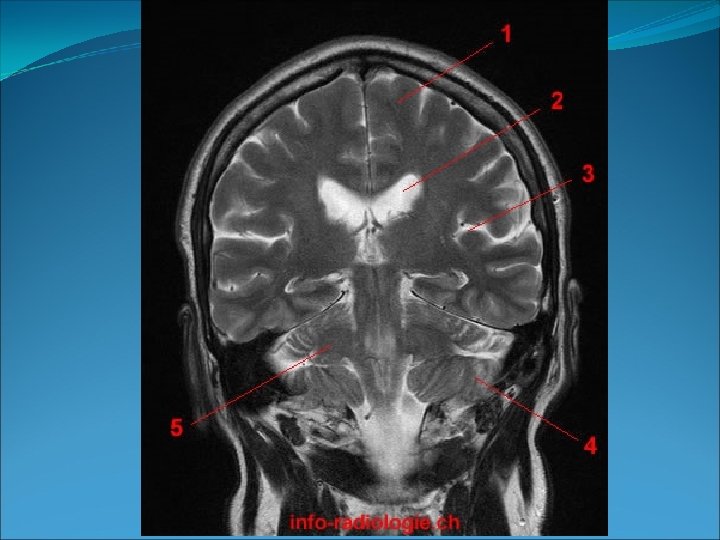

PLANOS, EJES Y MOVIMIENTOS Los planos son superficies imaginarias que dividen al cuerpo. Son 4: • Plano frontal o coronal: es un plano vertical que divide el cuerpo en dos partes, la anterior y la posterior. 6. Eje transversal. 7. 7 Eje longitudinal.